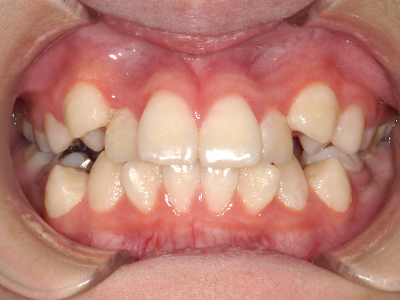

歯並びの相談に来られるお子様は、口呼吸をしているケースが多く、これが歯並びに大きな影響を与えています。

- 口呼吸をしている

↓ - 舌の位置が悪くなる

↓ - 頬の圧力が上の歯列にかかりやすくなる

↓ - 上あごが狭くなる

↓ - 下あごが狭くなる・下あごの位置が悪くなる

↓ - さまざまな不正咬合が生じる

ないき歯科クリニックでは、上あごの成長不足を補い、鼻呼吸を獲得しつつ歯列を整え、将来のお口をより健康な状態にすることをゴールに定める矯正治療をおこなっています。